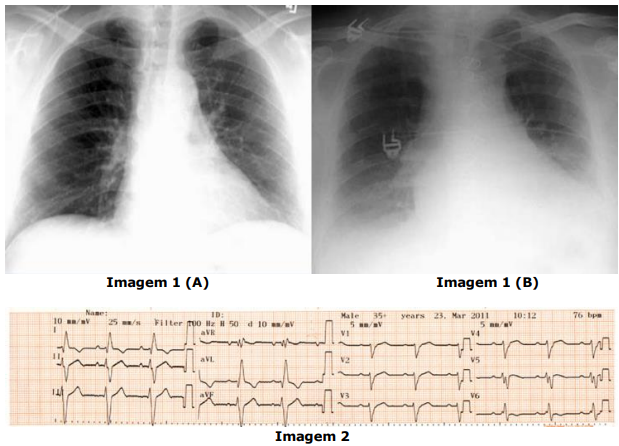

Considerando as imagens abaixo, analise as assertivas a seguir, assinalando V, se

verdadeiras, ou F, se falsas.

( ) A imagem 1 (A) é de um raio-X em projeção posteroanterior (PA) e é a projeção mais adequada para a avaliação do átrio esquerdo e ventrículo direito.

( ) A imagem 1 (B) é de um raio-X em projeção anteroposterior (AP) e é a projeção mais adequada para a avaliação do ventrículo esquerdo.

( ) O raio-X de tórax se tornou obsoleto para avaliação de cardiopatias após o desenvolvimento do ecocardiograma bidimensional, inclusive sendo substituído por ele na avaliação de insuficiência cardíaca pelos critérios de Framingham e de Boston.

( ) A velocidade de registro no eletrocardiograma da imagem 2 é de 50 mm/s.

( ) A amplitude do eletrocardiograma da imagem 2 é de 10 mm/mV.

( ) No eletrocardiograma da imagem 2, a onda P é positiva em DII e aVF e negativa em aVR, sugerindo origem a partir do nó sinusal.

A ordem correta de preenchimento dos parênteses, de cima para baixo, é:

( ) A imagem 1 (A) é de um raio-X em projeção posteroanterior (PA) e é a projeção mais adequada para a avaliação do átrio esquerdo e ventrículo direito.

( ) A imagem 1 (B) é de um raio-X em projeção anteroposterior (AP) e é a projeção mais adequada para a avaliação do ventrículo esquerdo.

( ) O raio-X de tórax se tornou obsoleto para avaliação de cardiopatias após o desenvolvimento do ecocardiograma bidimensional, inclusive sendo substituído por ele na avaliação de insuficiência cardíaca pelos critérios de Framingham e de Boston.

( ) A velocidade de registro no eletrocardiograma da imagem 2 é de 50 mm/s.

( ) A amplitude do eletrocardiograma da imagem 2 é de 10 mm/mV.

( ) No eletrocardiograma da imagem 2, a onda P é positiva em DII e aVF e negativa em aVR, sugerindo origem a partir do nó sinusal.

A ordem correta de preenchimento dos parênteses, de cima para baixo, é: